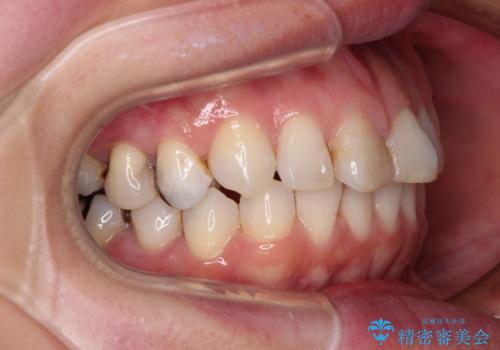

- 前歯のデコボコを治したいとのことで来院された患者様です。

上下顎ともに歯列全体の後方移動とIPR(歯と歯の間を削る)によってデコボコが解消するように設計し、インビザラインにより治療を行うこととしました。

しっかりと装着時間を守ってくださったのですが、途中妊娠にともなう悪阻や出産といったイベントがあり、予定よりも治療期間が長くなりました。